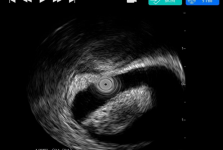

山东大学齐鲁医院(青岛)消化内科是在山东大学齐鲁医院消化内科的历史传承下,乘青岛院区的发展契机建立的。齐鲁医院消化内科早在20世纪年代由全国著名消化内科专家赵宪邨教授创建,经过几代人的共同努力,已发展成山东省消化学带头学科。... 查看更多